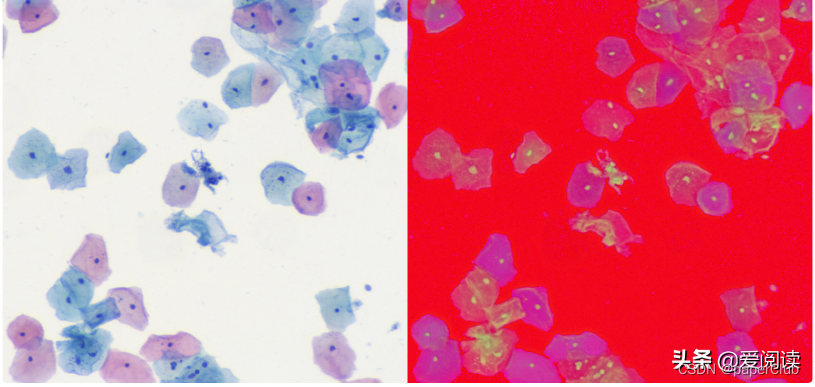

我们先拿到hsv图像, 完成细胞区域分离:

细胞区域初步分割结果: